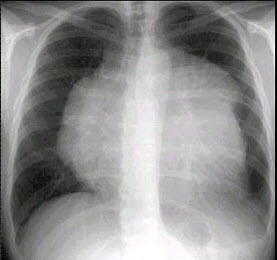

38、单项选择题

男,74岁,咳嗽,咳痰1月余,咯血丝痰1周伴胸痛,胸片如图,最可能的诊断为()